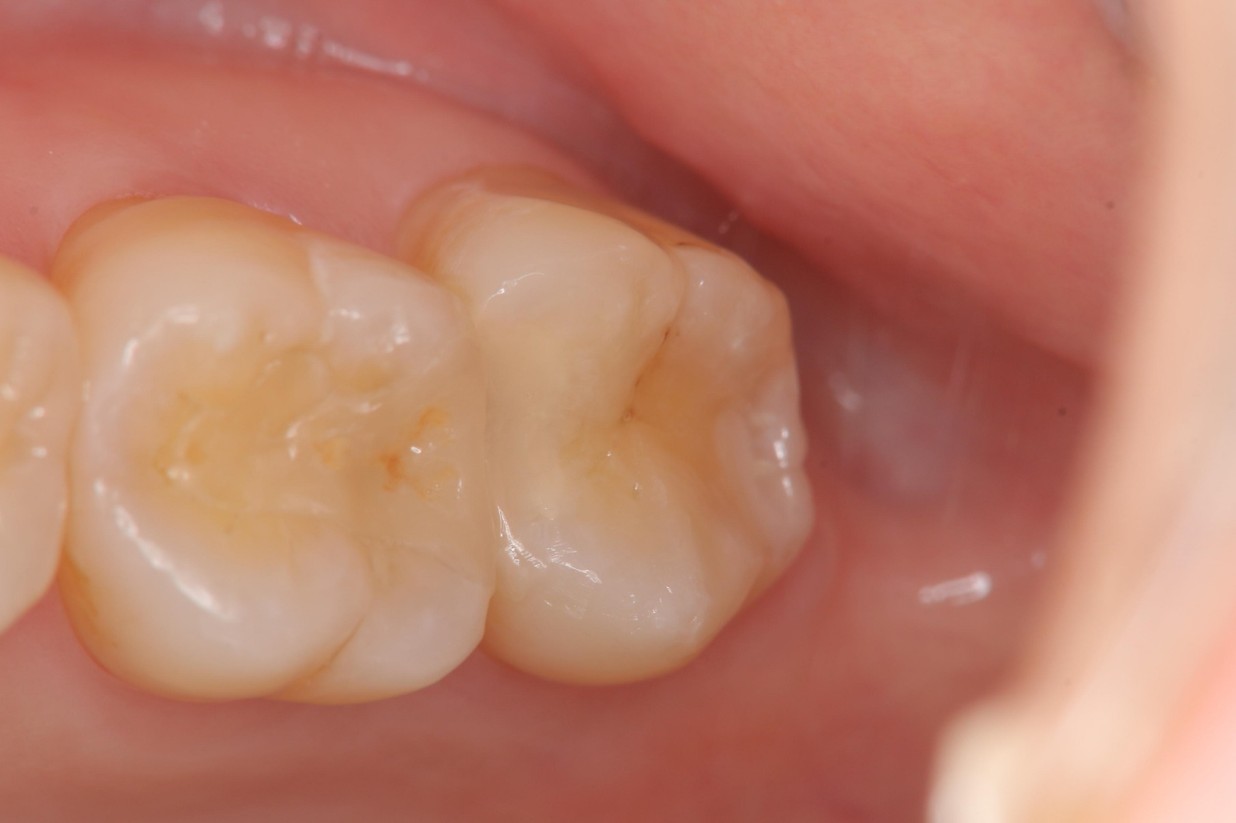

治療後,患者適應良好

當蛀牙破壞程度大,陶瓷崁體是根據蛀牙的窩洞量身訂做,不管是顏色、精密度都是最佳的選擇,因此是非常美觀與持久的填補窩洞材料與技術。